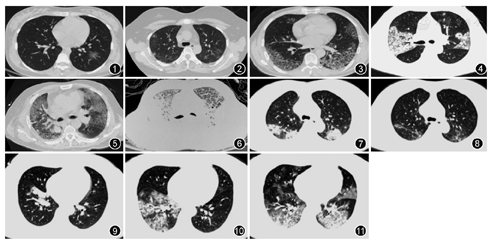

根据29例2019-nCoV肺炎患者的CT影像学表现,总结较为典型的征像如下(图1,图2,图3,图4,图5,图6):(1)单发磨玻璃阴影(GGO);(2)多发外周带磨玻璃阴影;(3)双肺斑片状GGO伴节段性肺实变;(4)铺路石征;(5)双肺弥漫性磨玻璃阴影伴支气管充气征;(6)双肺大面积实变影伴小叶间质增厚。部分患者CT影像学可呈如下动态改变:(1)早期:病变局限,呈斑片状、亚段或节段性磨玻璃影,多伴有小叶间隔增厚;(2)进展期:病灶增多、范围扩大,累及多个肺叶,部分病灶实变,磨玻璃影与实变影或条索影共存,有时会出现"铺路石征";(3)重症期:双肺弥漫性病变,少数呈"白肺"表现,实变影为主,合并磨玻璃影,多伴条索影,支气管充气征。根据临床分型标准[3],29例确诊患者分为普通型患者15例,重型患者9例(其中1例为孕妇)和危重型患者5例(其中肺癌术后1例)。在15例普通型患者中,有9例患者通过抗病毒+抗细菌+支持治疗,肺部病变明显或者部分吸收,病情缓解(图7,图8)。在14例重型和危重型患者中,7例影像学显示有明显的疾病进展(图9,图10,图11),其中有2例死亡。

在本研究中,我们分析了29例确诊为2019-nCoV肺炎患者的临床资料,总结该疾病的临床特征:(1)绝大多数患者都有不同程度的发热,多数伴有呼吸道症状。本组病例也有很多患者具有非呼吸系统症状,包括头痛、腹泻及乏力等,因而发热门诊医师需要高度重视非呼吸系统症状的识别。29例病例中死亡2例,分别为合并了肺癌和细菌感染。Guo等[12]发现病毒性肺炎的患者有基础疾病、有混合细菌感染时病死率增加,该研究结果与本研究结果一致。(2)外周血中,多数患者白细胞总数正常或减低,淋巴细胞计数减少。很多患者血清中LDH表达水平增高。多数患者C反应蛋白升高,降钙素原一般正常。严重者淋巴细胞进行性减少。在当前严峻的疫情下,我们推荐每个发热患者都需做高分辨率CT(HRCT)而不是X线胸片,因为X线胸片常常会遗漏早期病变。尽管病毒性肺炎的放射学表现一般被认为是非特异性的,很难与其他感染相鉴别[13]。但是,学者研究发现冠状病毒性肺炎仍具有一定较为特别的CT表现,如早期为多发片状磨玻璃状阴影,其内纹理可呈网格状改变[14,15]。本组很多患者具有典型的CT表现:早期呈单发或多发的斑片状磨玻璃影,伴有小叶间隔增厚;进展期表现为病灶增多、范围扩大,磨玻璃影与实变影或条索影共存;重症期表现为双肺弥漫性病变,少数呈"白肺"表现,以实变影为主,合并磨玻璃影,多伴条索影以及空气支气管征。胸腔积液或淋巴结肿大少见[9]。当临床医师遇到快速进展性肺炎患者时,若患者HRCT具有上述较为典型的影像学特征,再结合感染风险和当下流行病学资料,对诊断2019-nCoV肺炎是很有帮助的。虽然不能仅根据影像学特征作出最终诊断,但临床和影像学的结合可以极大地提高对该病诊断的准确性。